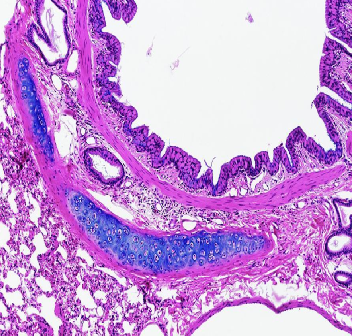

Trachea

(low power view)

Blue- Hyaline cartilage

Green- epithelium

Yellow- Glands in submucosa